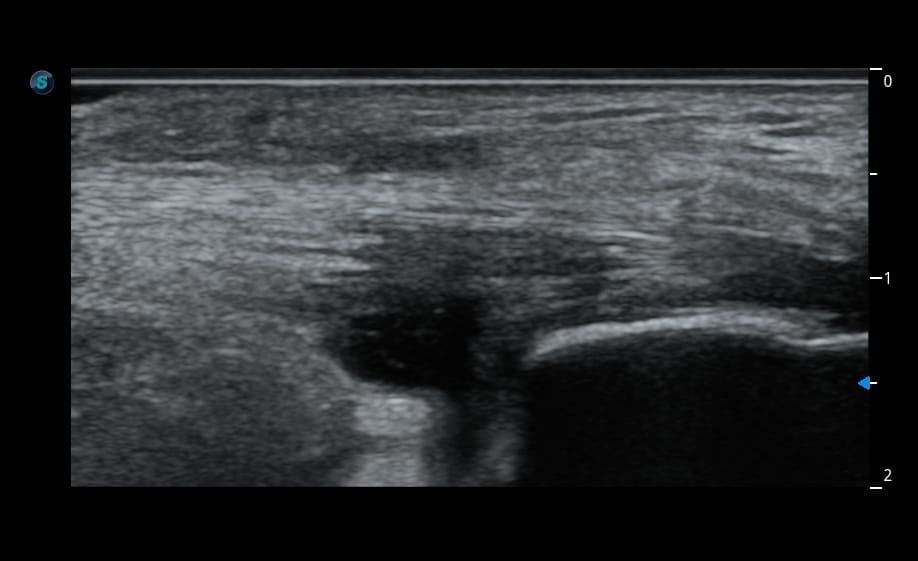

Une cheville en urgence

À l’examen, sa cheville est impossible à mobiliser tant elle est douloureuse. Elle m’explique que la douleur dure depuis plusieurs semaines, mais qu’elle n’a pas eu le temps de consulter en raison de la situation de son père.

Je décide donc de réaliser immédiatement une échographie musculo-squelettique en urgence de sa cheville, en parallèle de la gestion administrative de son père.

Résultat : des images surprenantes du tendon d’Achille chez une patiente jeune, qui font de ce cas une situation particulièrement intéressante à analyser.

Faites travailler votre œil et votre raisonnement avant la correction.

Quel est votre diagnostic ?

Analysez les images, repérez les éléments discriminants, puis confrontez votre hypothèse au raisonnement détaillé.